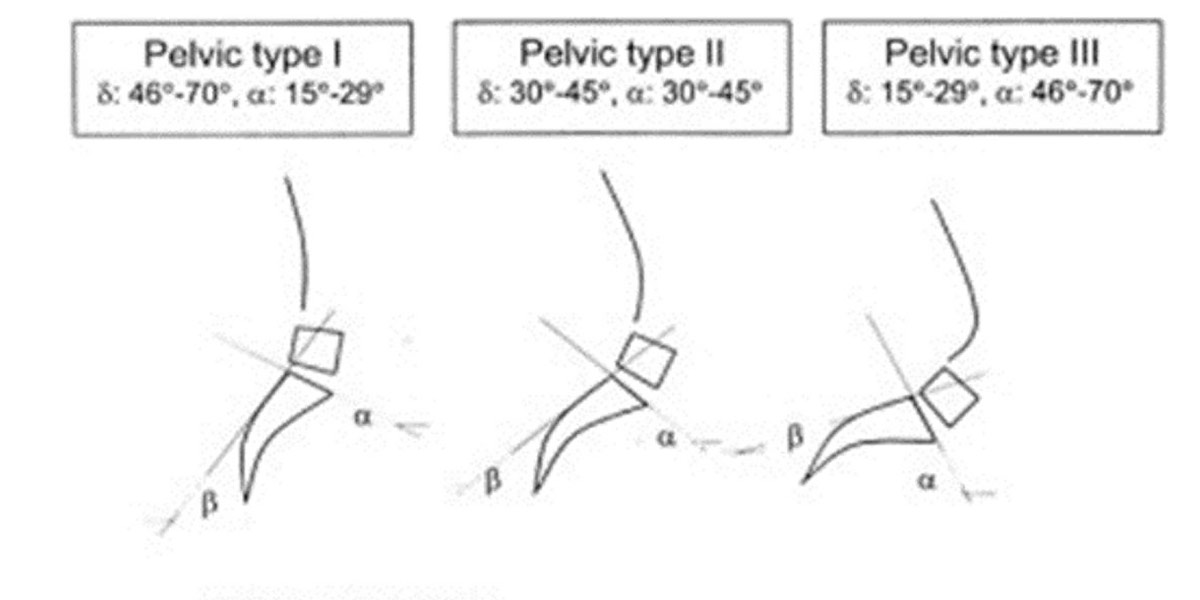

Eixo do joelho-coluna vertebral

Esta é uma causa menos grave, embora se tenha verificado que aquelas que pessoas que sofrem com a síndrome do joelho de corredor possuem uma inclinação menor do sacro que é o osso “soldado” que se encontra na parte inferior da nossa coluna.

Figura X. 3 tipos de pélvis segundo o grau de inclinação sacra.